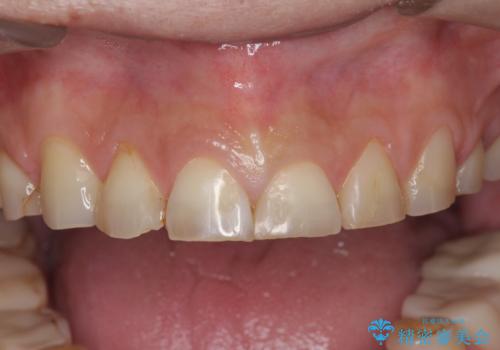

歯ぎしりですり減った 前歯の見た目を回復したい

- 歯ぎしり・嘔吐症により歯がすり減ってしまい、色調・見た目を改善したいと来院されました。

- 145.2万円(仮歯・ジルコニアクラウン×12歯)費用は治療当時の料金となります